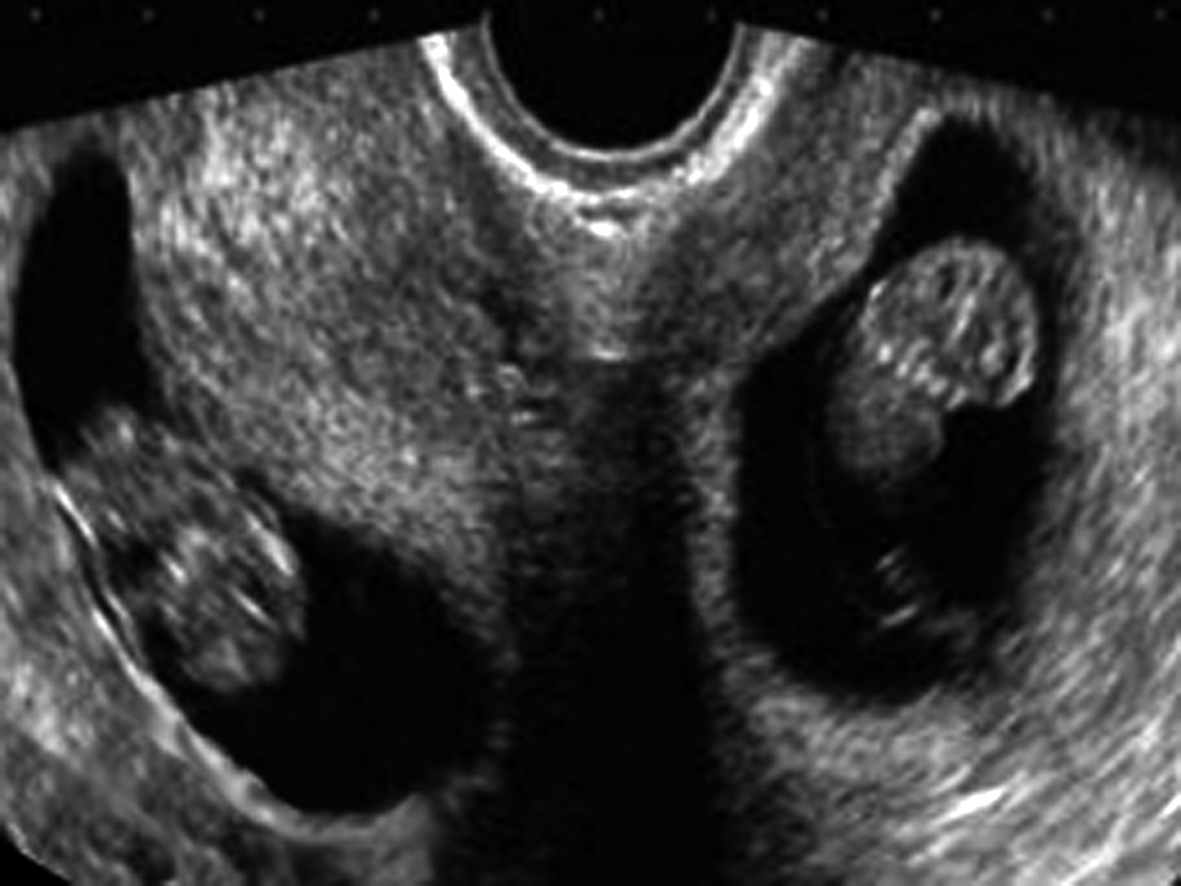

(五)羊水评估

对于双胎妊娠羊水的超声评估,目前还缺少理想的方法。辨认双胎之间的膜状分隔是评价双胎各自羊水状况的前提。在单胎妊娠中使用的主观评估、羊水池垂直深度、羊水指数等方法都可以在双胎妊娠中使用,注意辨认、分别评估各自的羊水状况是重要的,但多数是比较困难的。怀疑羊水过多或过少时,要分别垂直测量羊水池的最大值。当羊水测值最大深度<2cm时为羊水过少,>8cm时为羊水过多。